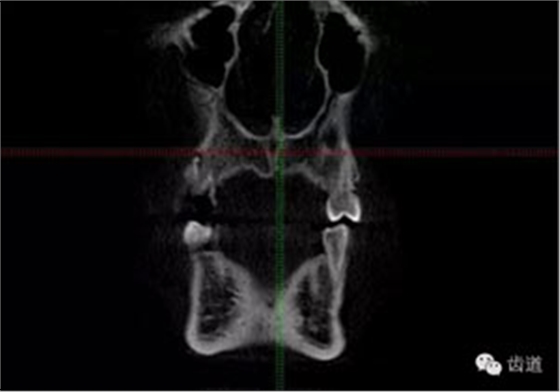

處理:1.建議CBCT檢查。

好的開(kāi)始就是成功的一半。通過(guò)CBCT了解根管的位置,形態(tài),方向。

檢查顯示:近頰及腭根充填恰填,遠(yuǎn)頰根管內(nèi)有少許充填物影像。根尖明顯低密度影像。